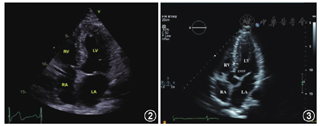

探头置于心尖搏动处,声束指向右侧胸锁关节,与左心长轴切面基本垂直,使图像扇形尖端位于心尖部,扇面指向心底部,心脏十字交叉位于图像中央,同时显示四个心腔,二尖瓣和三尖瓣位于左右排列,即为心尖四腔心切面。在心尖四腔心切面基础上,探头依次逆时针旋转约60°,可依次获得心尖两腔心切面和心尖三腔心切面(图1)。心尖四腔心切面是显示心脏主要解剖结构最重要的标准切面之一。心脏的四个心腔,左、右心房室瓣,房、室间隔及肺静脉、冠状静脉窦和心包膜等心血管结构均可在此切面上显像[1,2,3]。

注:RV右心室;TV三尖瓣;RA右心房;LV左心室;MV二尖瓣;LA左心房;AV主动脉瓣;AO主动脉

探头置于心尖搏动处,方向指向右胸锁关节,使图像扇形尖端位于心尖部,扇面指向心底部,心脏十字交叉位于图像中央(图2)。获取此切面时最容易犯的错误是探头位置偏上而没有位于心尖部,图像中的心尖部圆钝样而未显示真正心尖,即"切心尖"现象(视频1)。扇形切面中左心室心尖部是否为"尖形"以及心底部是否可以观察到右上肺静脉是判断探头是否位于心尖的常用方法。

注:RV右心室;RA右心房;LV左心室;LA左心房;LVOT左心室流出道;AV主动脉瓣

图像右侧自上向下依次为左心室、二尖瓣、左心房;左侧为右心室、三尖瓣、右心房,中央为室间隔、房间隔。其他结构如右上肺静脉以及右房内下腔静脉瓣可由此切面显示。

探头位置及其指向基本与心尖四腔心切面相同,但稍微将探头向上倾斜,在四腔心断面的图像中央十字交叉处出现左心室流出道和近端主动脉根图像,即出现第5个心血管腔(图3)。

主动脉根部位于两侧心房之间,左心室流出道位于左心室底部靠近室间隔的部位,其内侧为室间隔,连接主动脉根的内侧壁,外侧为二尖瓣前叶,与主动脉根外侧壁相连续,在主动脉根内可观察到主动脉瓣。